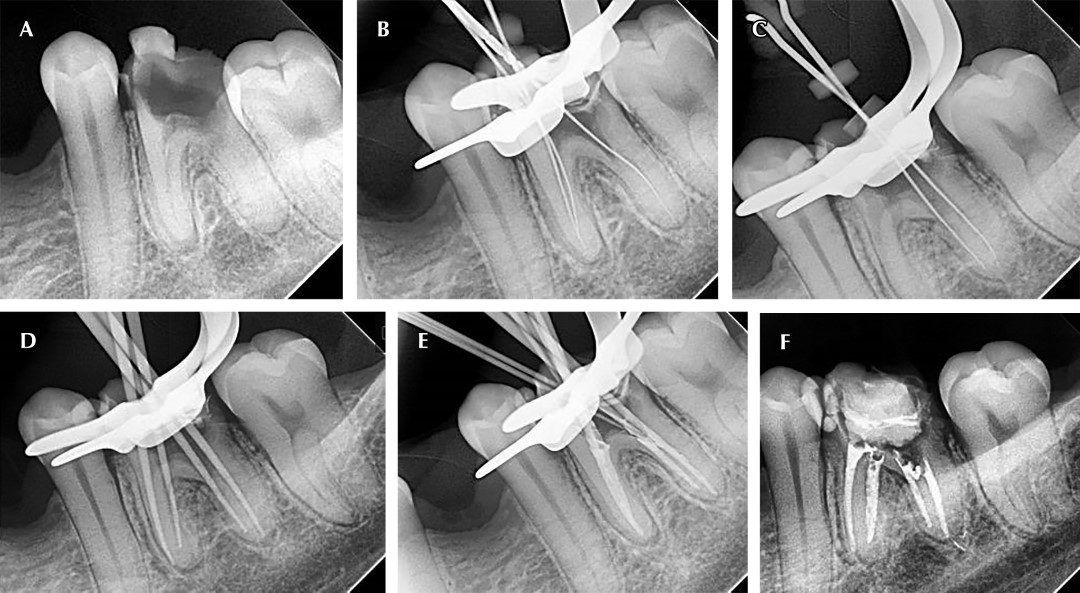

Paciente de 22 años de edad que acude a consulta dental por presentar fractura de la pared lingual del órgano dentario 36 (Figura 1A).

En la primera cita se logran patentizar los conductos mesiovestibular (MV), mesiolingual (ML) y distolingual (DL) (Figura 1B y C ), se toma longitud de trabajo, se procede a realizar la instrumentación con limas Af rotary hasta una conicidad 35.04, el conducto DV no se logra permeabilizar en esa cita; se coloca medicación con hidróxido de calcio en los conductos permeables, se cita al paciente al siguiente día para trabajar en conducto MV.

En la segunda cita se logra permeabilizar el conducto distovestibular (DV), se toma longitud de trabajo, se instrumenta y desinfecta, seguido de la colocación de medicación intraconducto con hidróxido de calcio.

El paciente es citado ocho días después de la medicación intraconducto, se realiza la remoción del hidróxido de calcio y se procede a realizar la obturación de los conductos radiculares con técnica de condensación lateral, utilizando como cemento sellador Ah plus y gutapercha (Figura 1D-F).

Figura 1